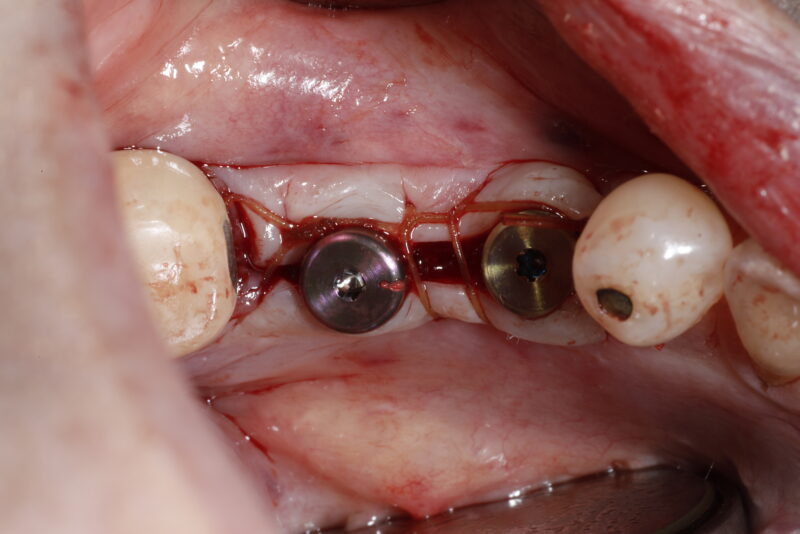

• Hello everyone! I hope everyone’s having a great week. Here’s an update to the previous case that was shared and has been discussed.

Look how much thick keratinized tissue there is now once the patient is fully healed five months postoperatively. We also had good bone regeneration around and over the implants and placed wide healing abutments…

Read more